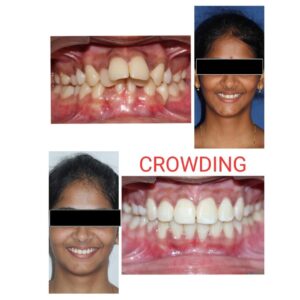

⦿ Orthodontics (Full time Specialist available)

. Fixed appliances

. Conventional Braces

. Lingual Braces

. Clear Aligners